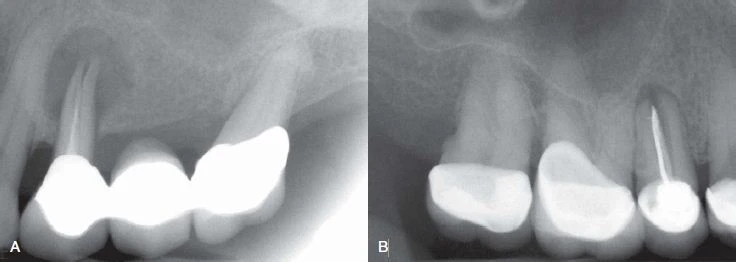

Hình 9. Đôi khi không có dấu hiệu rõ ràng cho thấy lý do răng có triệu chứng. (A) Hình ảnh X quang cho thấy răng cối lớn thứ hai hàm dưới có miếng trám sâu mức độ trung bình. (B) Thử tuỷ cho thấy răng chết tuỷ. Không chiếu sáng nên không thấy có đường nứt nào cả. (C) Chiếu ánh sáng có cường độ cao lên bề mặt răng, quan sát thấy vết nứt ở mặt ngoài. (D) Chiếu sáng vào mặt xa – trong của răng.